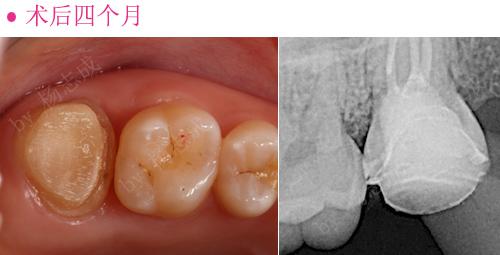

术前

术后